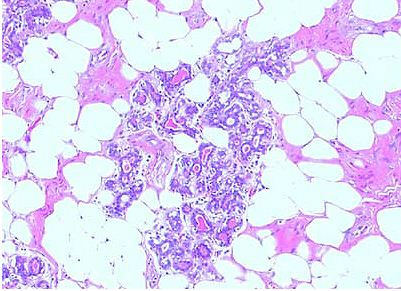

此例有包膜,肿瘤内乳腺小叶基本正常,腺体没有明显的增生,上皮细胞、肌上皮细胞都是完整的。不像腺瘤。还是比较符合纤维腺瘤这个范畴的,查了下书,《中华外科病理学》提到乳腺纤维腺瘤的间叶成分中有时可以出现纤维组织以外的结缔组织成分,较多出现的是脂肪组织,也可以出现化生的骨、软骨、平滑肌等成分。此时也常被诊断为错构瘤。

另外网上搜了一下,查到一篇影像学杂志的类似的钼靶x光诊断乳腺纤维腺脂肪瘤的个案报道,本例纤维成分比较少,但是小叶内还是有少量的纤维组织。我想要么下错构瘤,要么下纤维腺脂肪瘤的诊断合适些了。